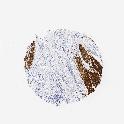

STOMACH CANCER - Protein expressioni

A mouse-over function shows sample information and annotation data. Click on an image to view it in a full screen mode. Samples can be filtered based on level of antibody staining by selecting one or several of the following categories: high, medium, low and not detected. The assay and annotation is described here.

Note that samples used for immunohistochemistry by the Human Protein Atlas do not correspond to samples in the TCGA dataset.

Antibody stainingi

Antibody staining in the annotated cell types in the current human tissue is reported as not detected, low, medium, or high, based on conventional immunohistochemistry profiling in selected tissues. This score is based on the combination of the staining intensity and fraction of stained cells.

Each image is clickable and will lead to virtual microscopy that enables deeper exploration of all samples and also displays staining intensity scores, fraction scores and subcellular localization as well as patient and tissue information for each sample.

Antibody HPA008066

Antibody HPA017330

Antibody CAB000006

Staining

High

Medium

Low

Not detected

Intensity

Strong

Moderate

Weak

Negative

Quantity

>75%

75%-25%

<25%

None

Location

Nuclear

Cytoplasmic/membranous

Cytoplasmic/membranous,nuclear

Adenocarcinoma, NOS